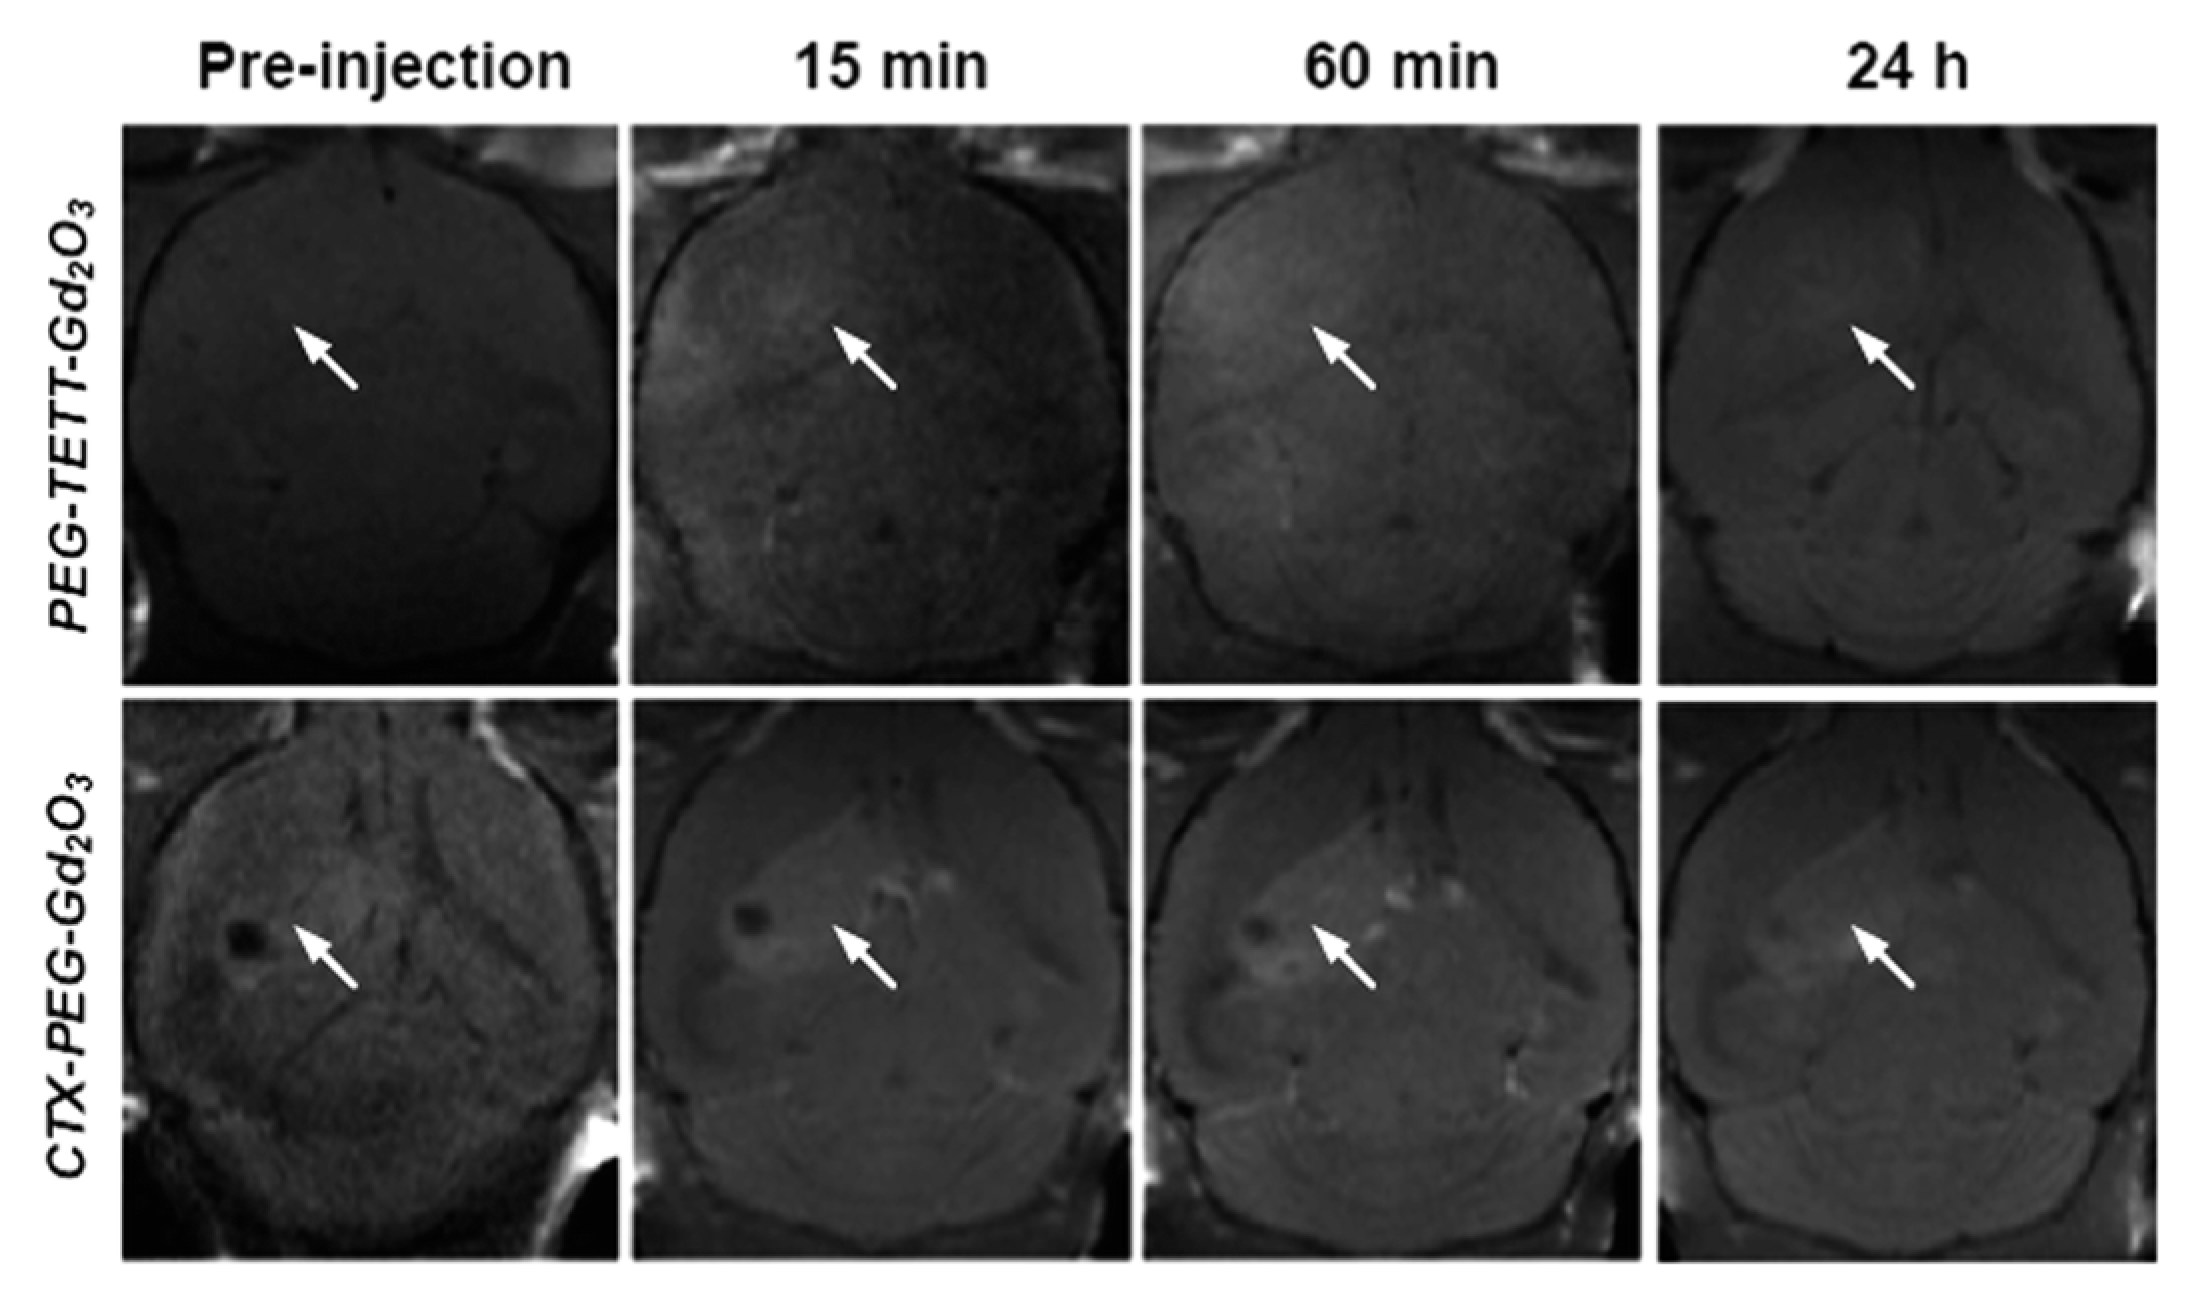

- Gu, W.; Song, G.; Li, S.; Shao, C.; Yan, C.; Ye, L. Chlorotoxin-conjugated, PEGylated Gd2O3 nanoparticles as a glioma-specific magnetic resonance imaging contrast agent. RSC Adv. 2014, 4, 50254–50260. [Google Scholar] [CrossRef]